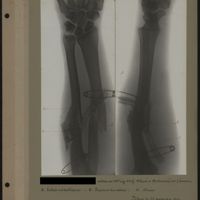

0013 - Page 9 - [Radiographies de l'avant-bras]0013 - Page 9 - [Radiographies de l'avant-bras]